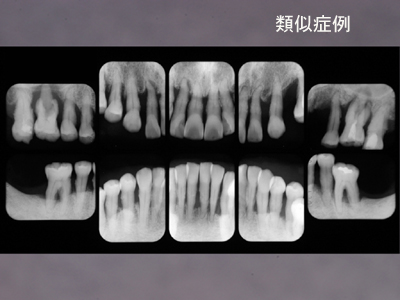

当院で歯周治療ののちメインテナンス10年以上継続している患者さんのなかで「初診時の状態ワースト10」の資料を集めてみました。

これら全て初診時のプラークスコア80%以上、プロービングデプス7mm以上が50~60%、4mm以上なら80%をゆうに超える重症例ばかりです。最年少は初診時37歳(これは侵襲性歯周炎もしくは急速進行性若年性歯周炎でしょう),その後18年のメンテナンス,というケースをはじめ、皆、私の歯科医としての想いを込めて治療、メインテナンスを続けてきた重症例ばかりですから細かい数字はともかく患者さんのプロフィールや治療経過、口腔内の状態等は空でいえます。当然、初診時は悪くても全て現在は良好な経過をたどっています。